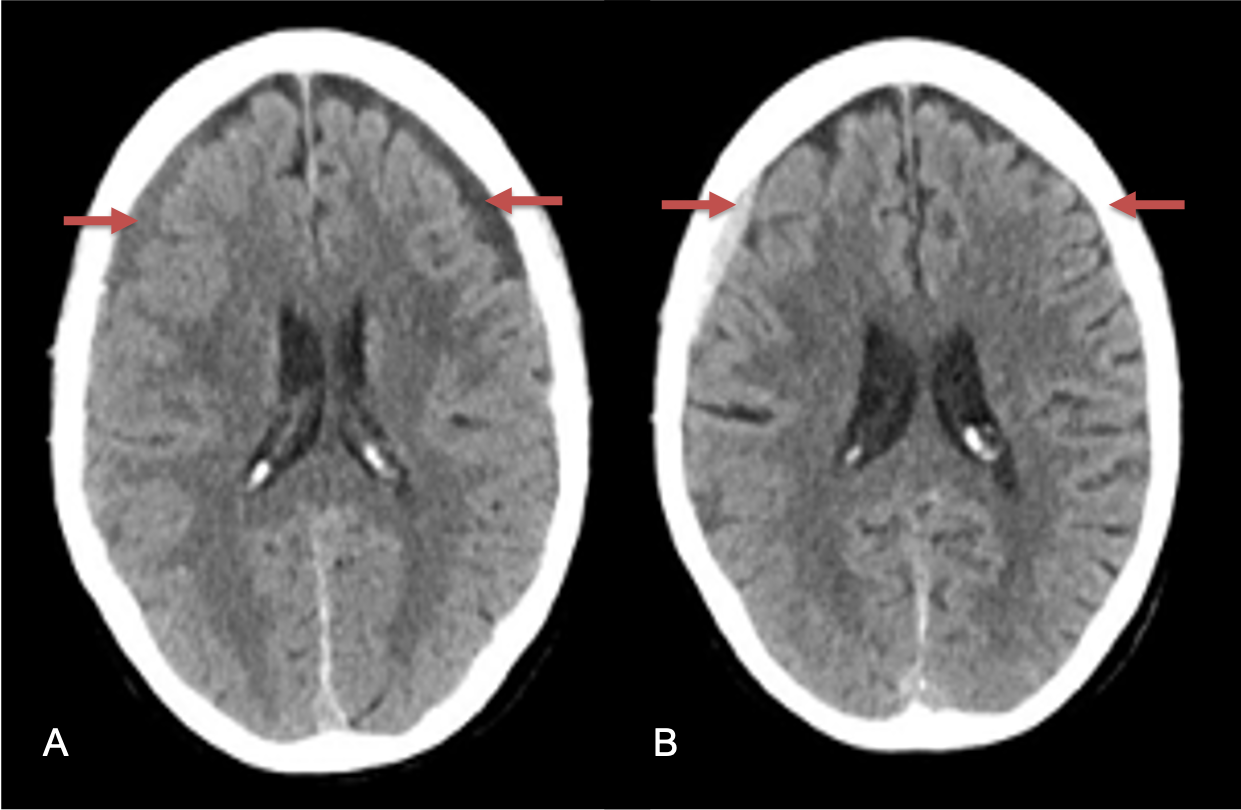

Figure 1. A) 6 weeks post mild trauma B) 4 weeks post mild trauma demonstrate stable subacute subdural collections with mild growth and sulcal effacement.

A man in his 80s developed mild dizziness and headache following incidental trauma working in his garage one day. He presented several weeks later to the ER and was diagnosed with bilateral subdural hematomas, which were initially managed with observation, low dose Decadron, considering the mildness of symptoms, advanced age, and history of CLL with thrombocyptopenia (<100k). Over the next 4 weeks, the collections remained relatively stable with evidence of slight growth (10 to 12 mm thickness, and 2 mm right to left shift) on NCT (Figure 1. A and B).